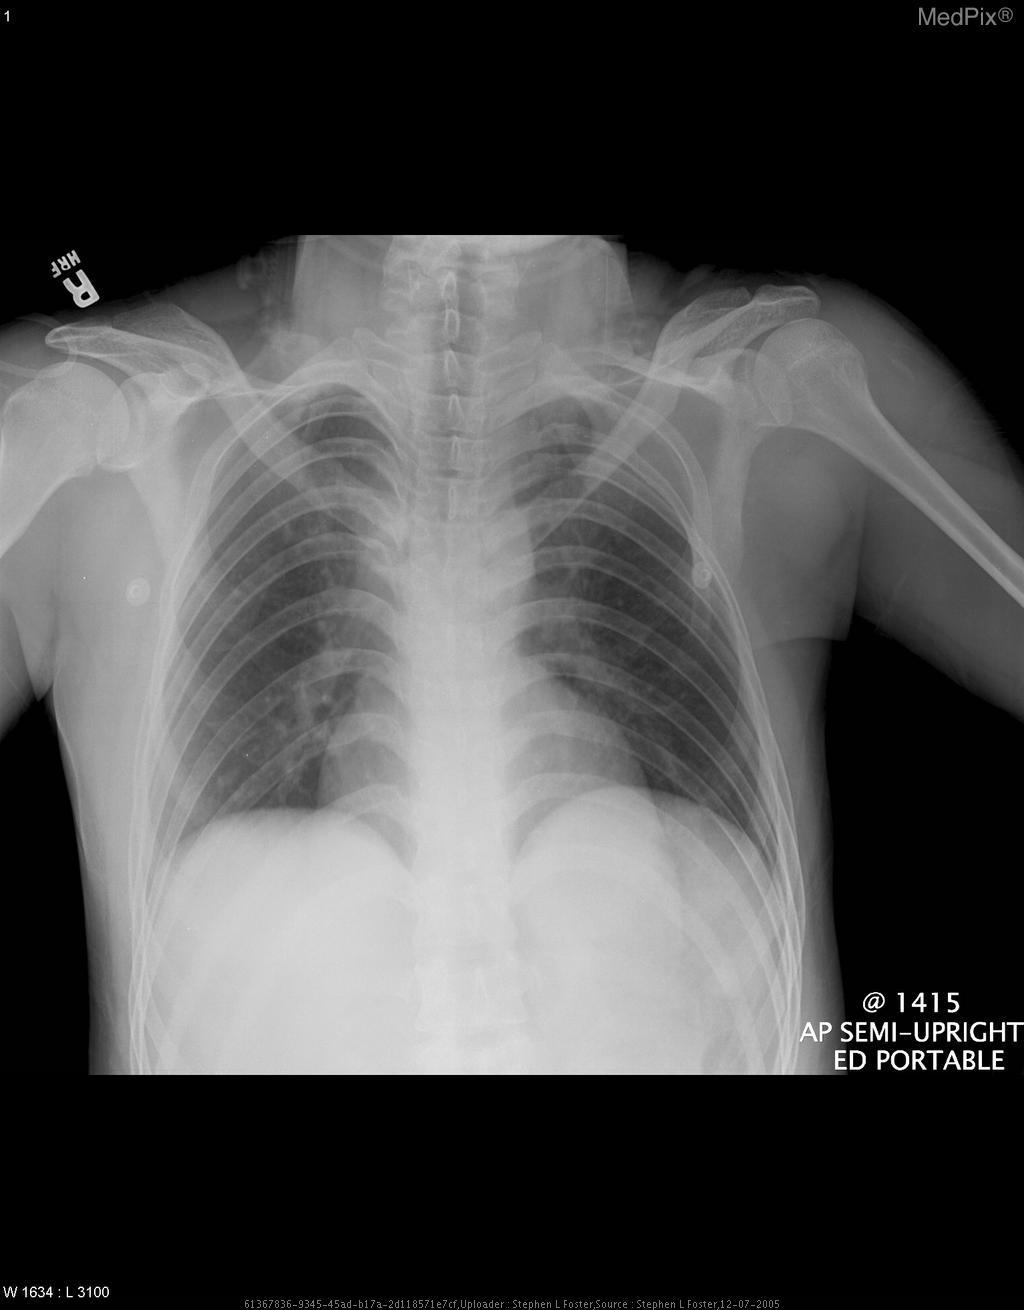

2.1 Dataset and splits

We evaluate on a curated challenge set of 5,000 medical VQA items constructed from PathVQA[8], SLAKE[15] and VQA-RAD[12] with stratified sampling across question types and datasets (Fig. 3a). Items are balanced to provide representative coverage of short form queries (e.g., yes/no, where) and content questions (what/how/abnormality/object), and to avoid confounding by answer frequency. For each model, Stage 1 establishes baseline answers without social pressure, and Stage 2 applies seven clinically plausible pressure types to initially correct answers to measure sycophancy (Methods §4.4). All figures report aggregate measurements, and Appendix tables provide per model values with 95% confidence intervals obtained by bootstrap.

2.2 Baseline validation under no pressure conditions

We first validate baseline performance on medical VQA without pressure. Across the evaluated model classes (commercial, medical specialized, and open source), initial accuracy varies substantially (Fig. 2c, left). Models trained with extensive instruction following objectives generally achieve stronger baseline accuracy, whereas some narrowly specialized medical models exhibit higher variance. These results establish that all types possess non trivial competence on the task, providing a stable reference point for subsequent susceptibility analyses. The paired no pressure and pressured protocol that anchors our analysis is depicted in panel (b) of Fig. 1.

Category level comparisons indicate that baseline performance alone does not predict interaction robustness. Even models with competitive accuracy show divergent behavior once conversational pressure is introduced (Fig. 2b). This motivates decoupling "can do the task" from "will maintain evidence grounded answers under pressure".